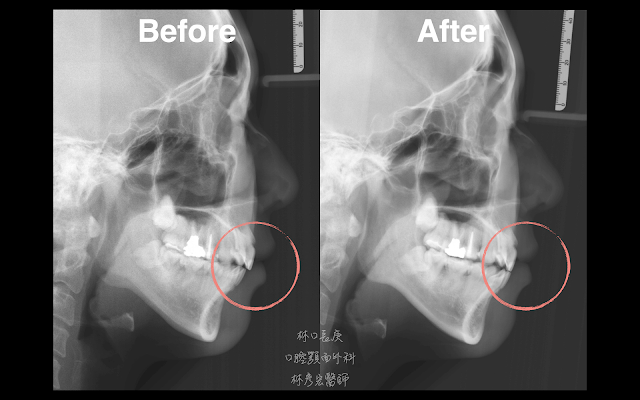

患者的環口X光片可以看到雙側顳顎關節髁頭明顯吸收變形、測顱X光片檢查也可看到下顎後縮合併上下前牙overjet過大的現象,這些都顯示患者雙側顳顎關節髁頭(condyle)不穩定的情形,於是建議患者接受雙側的微創顳顎關節內視鏡手術。

坦白說,手術中看到這樣的關節盤破裂,要在內視鏡下縫合復位是非常困難達到的,但每次做這樣的手術,林醫師總是盡力將關節盤縫合得越穩定越好,也許影像上看起來只是小小的位置上的改變,但實際上卻要花上非常多經驗與技術上的累積,這也是為什麼微創顳顎關節內視鏡縫合復位手術之所以非常困難的地方。所幸,這樣的堅持下能夠幫助到患者。像這位患者術後咬合overjet就立即獲得改善,下顎也有略為逆時鐘旋轉的效果,疼痛指數從7分(術前)變成0分(術後),準備接受二次矯正了呢!